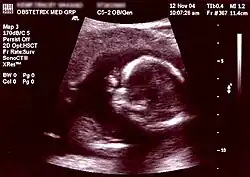

A ecografia é um exame seguro que não implica nenhum risco para a grávida ou para o feto e que permite detectar algumas doenças congénitas durante a fase inicial da gravidez, estimar com maior precisão a idade gestacional e a data prevista de parto e detetar uma gravidez múltipla.[74] A partir das cinco semanas e meia de gestação já é possível observar o embrião. Quando este atinge 5mm é possível observar o batimento cardíaco por ecografia pélvica, embora em alguns casos só seja visível quando atinge os 7mm, o que acontece por volta da 7ª semana.[75] As recomendações internacionais de saúde pública recomendam que seja realizada pelo menos uma ecografia de rotina a todas as grávidas entre as 18 e as 22 semanas de gestação (ecografia do segundo trimestre) e, em países com recursos, que seja também realizada uma ecografia de rotina entre as 11 semanas e as 13 semanas e seis dias de idade gestacional (ecografia do primeiro trimestre). Em alguns países realiza-se ainda uma ecografia de rotina entre as 30 e as 32 semanas (ecografia do terceiro trimestre). Em todas as ecografias de rotina de uma gravidez de baixo risco são avaliados o número de fetos e placentas, a atividade cardíaca, os movimentos fetais, a localização da placenta, a quantidade de líquido amniótico e os valores biométricos. Para além destes parâmetros gerais, em cada trimestre são também avaliados parâmetros específicos.[76][77][78][79]

Na ecografia do primeiro trimestre são geralmente avaliados o comprimento crânio-caudal, a frequência cardíaca do feto, a medida da translucência da nuca, se gémeos partilham ou não a placenta (corionicidade) e a anatomia do feto (pólo cefálico, coluna vertebral, estômago, parede abdominal e membros).[79] O comprimento crânio-caudal permite determinar a idade gestacional com uma precisão ligeiramente superior aos cálculos com base no último período menstrual. Uma vez determinada a idade gestacional por ecografia, não será alterada até ao fim da gravidez.[80] Durante a ecografia do primeiro trimestre é também calculado o risco de trissomia 21. Este risco é calculado através da ponderação conjunta do valor de translucência da nuca medido por ecografia, da idade da mãe e, sempre que possível, do rastreio por análises clínicas da fração livre da gonadotrofina coriónica humana e da proteína plasmática associada à gravidez. Este rastreio combinado identifica 90% dos casos de trissomia 21 e outras principais doenças congénitas.[81]

A ecografia do segundo semestre, ou ecografia morfológica, para além de confirmar alguns dados do primeiro trimestre, destina-se principalmente a identificar malformações do feto. São avaliados o contorno craniano e cérebro, face e pescoço, coração, pulmões, abdómen, coluna vertebral, membros, cordão umbilical e genitais externos. É possível distinguir o sexo do feto por ecografia a partir das 11 semanas de gestação. No entanto, só a partir das 13 semanas é que é possível fazê-lo com uma precisão entre 99% e 100%.[82] Na ecografia do terceiro trimestre são avaliados a apresentação fetal, o perímetro cefálico, perímetro abdominal, comprimento do fémur e vários parâmetros biofísicos.[79]